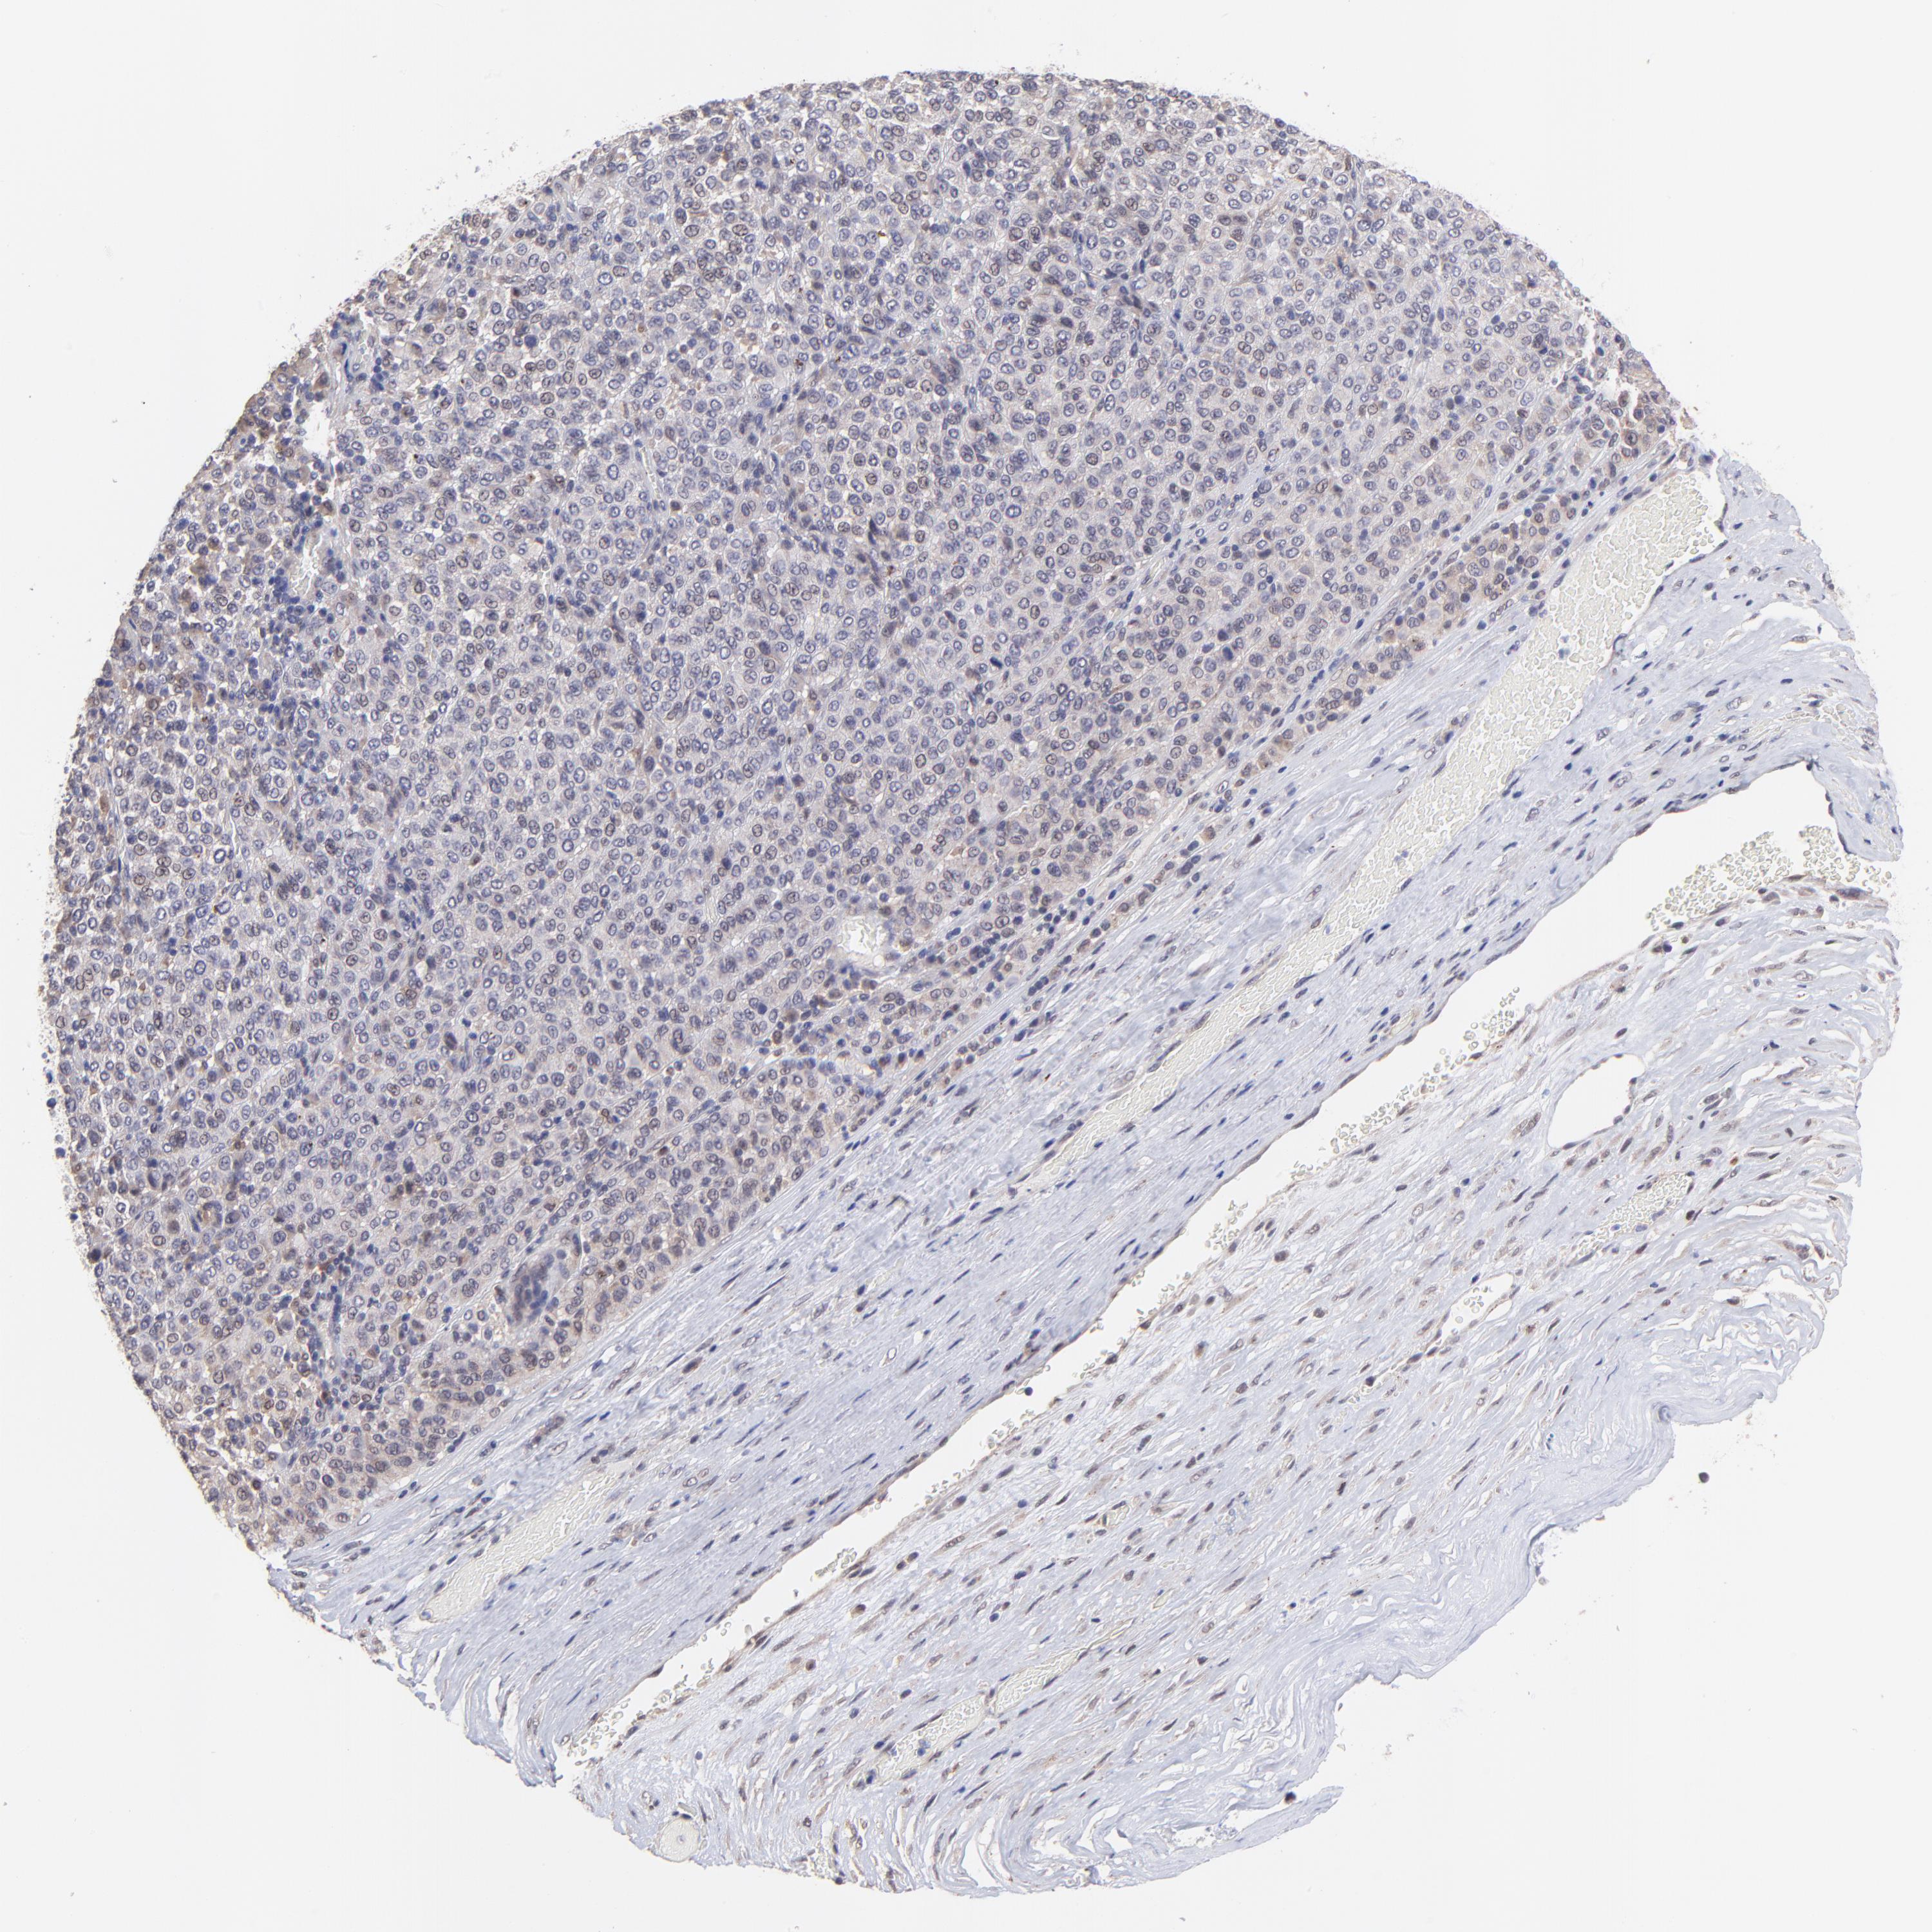

MELANOMA - Protein expressioni

A mouse-over function shows sample information and annotation data. Click on an image to view it in a full screen mode. Samples can be filtered based on level of antibody staining by selecting one or several of the following categories: high, medium, low and not detected. The assay and annotation is described here.

Note that samples used for immunohistochemistry by the Human Protein Atlas do not correspond to samples in the TCGA dataset.

Antibody stainingi

Antibody staining in the annotated cell types in the current human tissue is reported as not detected, low, medium, or high, based on conventional immunohistochemistry profiling in selected tissues. This score is based on the combination of the staining intensity and fraction of stained cells.

Each image is clickable and will lead to virtual microscopy that enables deeper exploration of all samples and also displays staining intensity scores, fraction scores and subcellular localization as well as patient and tissue information for each sample.

Antibody HPA003203

Staining

High

Medium

Low

Not detected

Intensity

Strong

Moderate

Weak

Negative

Quantity

>75%

75%-25%

<25%

None

Location

Nuclear

Cytoplasmic/membranous

Cytoplasmic/membranous,nuclear

Malignant melanoma, NOS

Malignant melanoma, Metastatic site